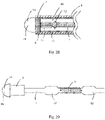

- Fig. 4 illustrates an embodiment of support spine 1 (or support wire) that is generally straight and that is appropriate for use in medical devices 20 that are generally straight (for example, medical device 20 of Fig. 1 ).

- An energy delivery device 15 and radiopaque markers 5 are attached to support spine 1 of Fig. 4 .

- the support spine has a plurality of evenly spaced markers attached thereto.

- the lumen containing support spine 1 is lumen 26 of elongate member 6, which is typically from about 60 cm to about 120 cm in length. In some embodiments the support spine 1 (or support wire) extends for a distance of about 10 cm (or about 4 inches).

- the support spine is typically somewhat (for example, a few millimeters) longer than a distal laser-cut section of elongate member 6 ( Fig. 6 ) to provide overlap with an uncut portion of elongate member 6.

- Typical embodiments of support spine 1 have a proximal portion that is straight.

- Alternative embodiments of the support spine 1 e.g. Figs. 27A and B

- Other alternative embodiments which also facilitate contact with elongate member 6 include the support spine being comprised of a spring, for example a helical spring or a leaf spring.

- Typical embodiments of support spine 1 have a constant outer diameter.

- Alternative embodiments of the support spine 1 can have a varying or non-constant outer diameter.

- the support spine tapers proximally to facilitate contact with elongate member 6 and thereby providing an alternative electrical path to electrode 19.

- support spine 1 are comprised of one wire.

- Alternative embodiments of support spine 1 are comprised of two or more wires joined side-by-side to provide a preferential bending direction or two or more wires braided together for greater strength and flexibility.

- support spine 1 are comprised of a solid wire.

- Alternative embodiments of support spine 1 are comprised of a ribbon to provide a preferential bending plane or direction.

- support spine 1 For ease of manufacturing, typical embodiments of support spine 1 have a circular cross-section. Alternative embodiments of support spine 1 can have non-circular cross-sections, for example, D-shaped, triangular, or rectangular, which have preferential bending directions.

- Support spine 1 provides stiffness to the flexible portion of medical device 20 while leaving lumen 26 sufficiently unobstructed for flow of fluid, such as contrast fluid for imaging purposes.

- Support spine 1 is comprised of nitinol and provides shape memory properties to the device.

- support spine 1 In some embodiments of medical device 20, in which elongate member 6 is normally biased to be straight, the shape memory properties and stiffness of support spine 1 allows medical device 20 to behave similarly to a guide-wire and to revert to a straight configuration after being bent. Such embodiments of support spine 1 also provide stiffness to balance the flexibility created by any cuts made into elongate member 6.

- support spine 1 An elongate configuration of support spine 1 is illustrated in Figs. 14 and 15 . Due to its elongate shape, support spine 1 is typically not self-supporting; rather, support spine 1 is typically floppy (i.e. loosely hanging at its proximal end).